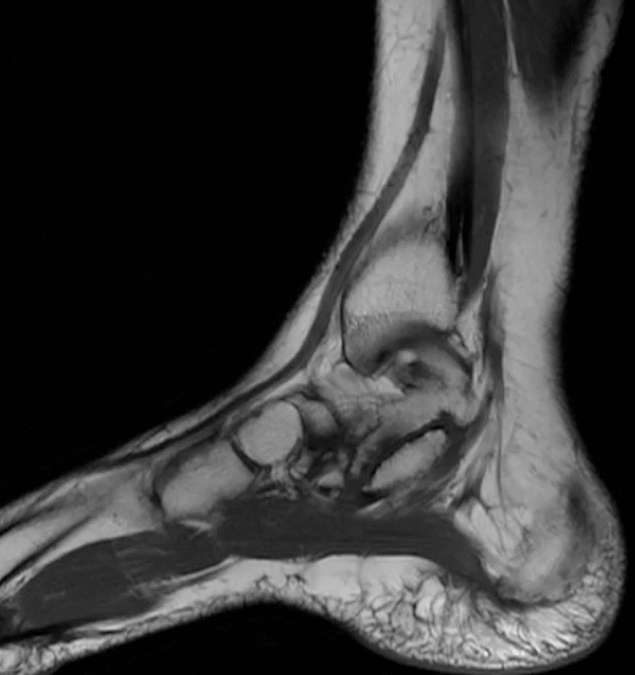

Épanchement (intra-articulaire et sentimental) – Poème IRM (vidéo-poèmes)

Novembre 2021. Que peut-on face à la vio­lence du lan­gage médi­cal lorsqu’on reçoit des résul­tats de san­té ? Pour ma part, je réponds avec mon propre lan­gage : un vidéo-poème, quasi-ready-made.

Remue​.net a publié mon “Poème-IRM”, dont le sous-titre est : “Epan­che­ment (intra-arti­cu­laire et sentimental)”.